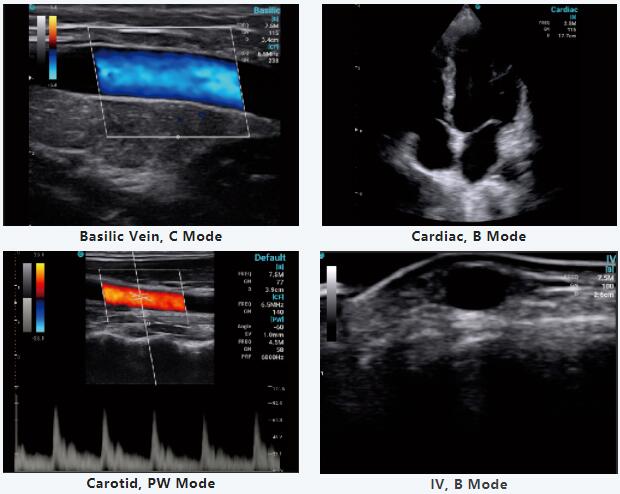

在这次特别的网络研讨会上,Jerome博士分享了他使用CHISON SonoEye的部分日常工作,通过他的视频,BB体育平台登录对SonoEye的便携性和精确的诊断印象深刻,并发现SonoEye在临床应用中的帮助有多大。

此外,Jerome博士还分享了SonoEye的创新功能,并对手持超声市场做出了全面、有价值的分析。手持式超声波的重要性和需求将继续增加,使优质医疗保健触手可及。